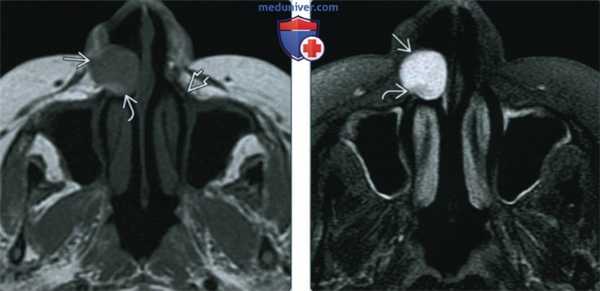

(Справа) При МРТ Т1ВИ в сагиттальной проекции визуализируется носогубная киста с диффузно гиперинтенсивным сигналом, хорошо отграниченная от окружающих тканей. Обратите внимание, что верхний край кисты расположен в непосредственной близости к нижней носовой раковине и дну преддверия носа. При исследовании этих образований обнаружено, что они имеют подслизистую локализацию. (Слева) При MPT Т1 в аксиальной проекции в пределах грушевидною отверстия визуализируется хорошо отграниченное объемное образование, распространяющееся в преддверие носа. Сигнал от образования слегка интенсивнее, чем от мышц, определяются фокусы гиперинтенсивною сигнала (белковый дебрис). Обратите внимание, что объемное образование вплотную прилежит к верхней челюсти и вызывает ее умеренно выраженную эрозию по сравнению с противоположной стороной.

(Справа) При MPT Т2 ВИ FS в аксиальной проекции визуализируется носогубная киста округлой формы с сигналом равномерной интенсивности, содержащая белковый дебрис со слегка гипоинтенсивным сигналом.

(Слева) При MPT Т1 в аксиальной проекции в пределах грушевидною отверстия визуализируется хорошо отграниченное объемное образование, распространяющееся в преддверие носа. Сигнал от образования слегка интенсивнее, чем от мышц, определяются фокусы гиперинтенсивною сигнала (белковый дебрис). Обратите внимание, что объемное образование вплотную прилежит к верхней челюсти и вызывает ее умеренно выраженную эрозию по сравнению с противоположной стороной.

(Слева) На аксиальной МРТ (Т1 ВИ) определяется хорошо отграниченное образование в грушевидной вырезке, распространяющееся в преддверие носа. Сигнал в образовании слегка более интенсивен по сравнению с мышцей, в нем видны гиперинтенсивные очаги, вероятно, представляющие собой белковый дебрис. Обратите внимание на поражение верхней челюсти с небольшими эрозиями костей с противоположной стороны.

(Справа) На аксиальной МРТ (Т2 ВИ FS) у этого же пациента определяется носогубная киста с типичным однородным гиперинтенсивным Т2 сигналом и слабо различимым гипоинтенсивным включением белкового дебриса.